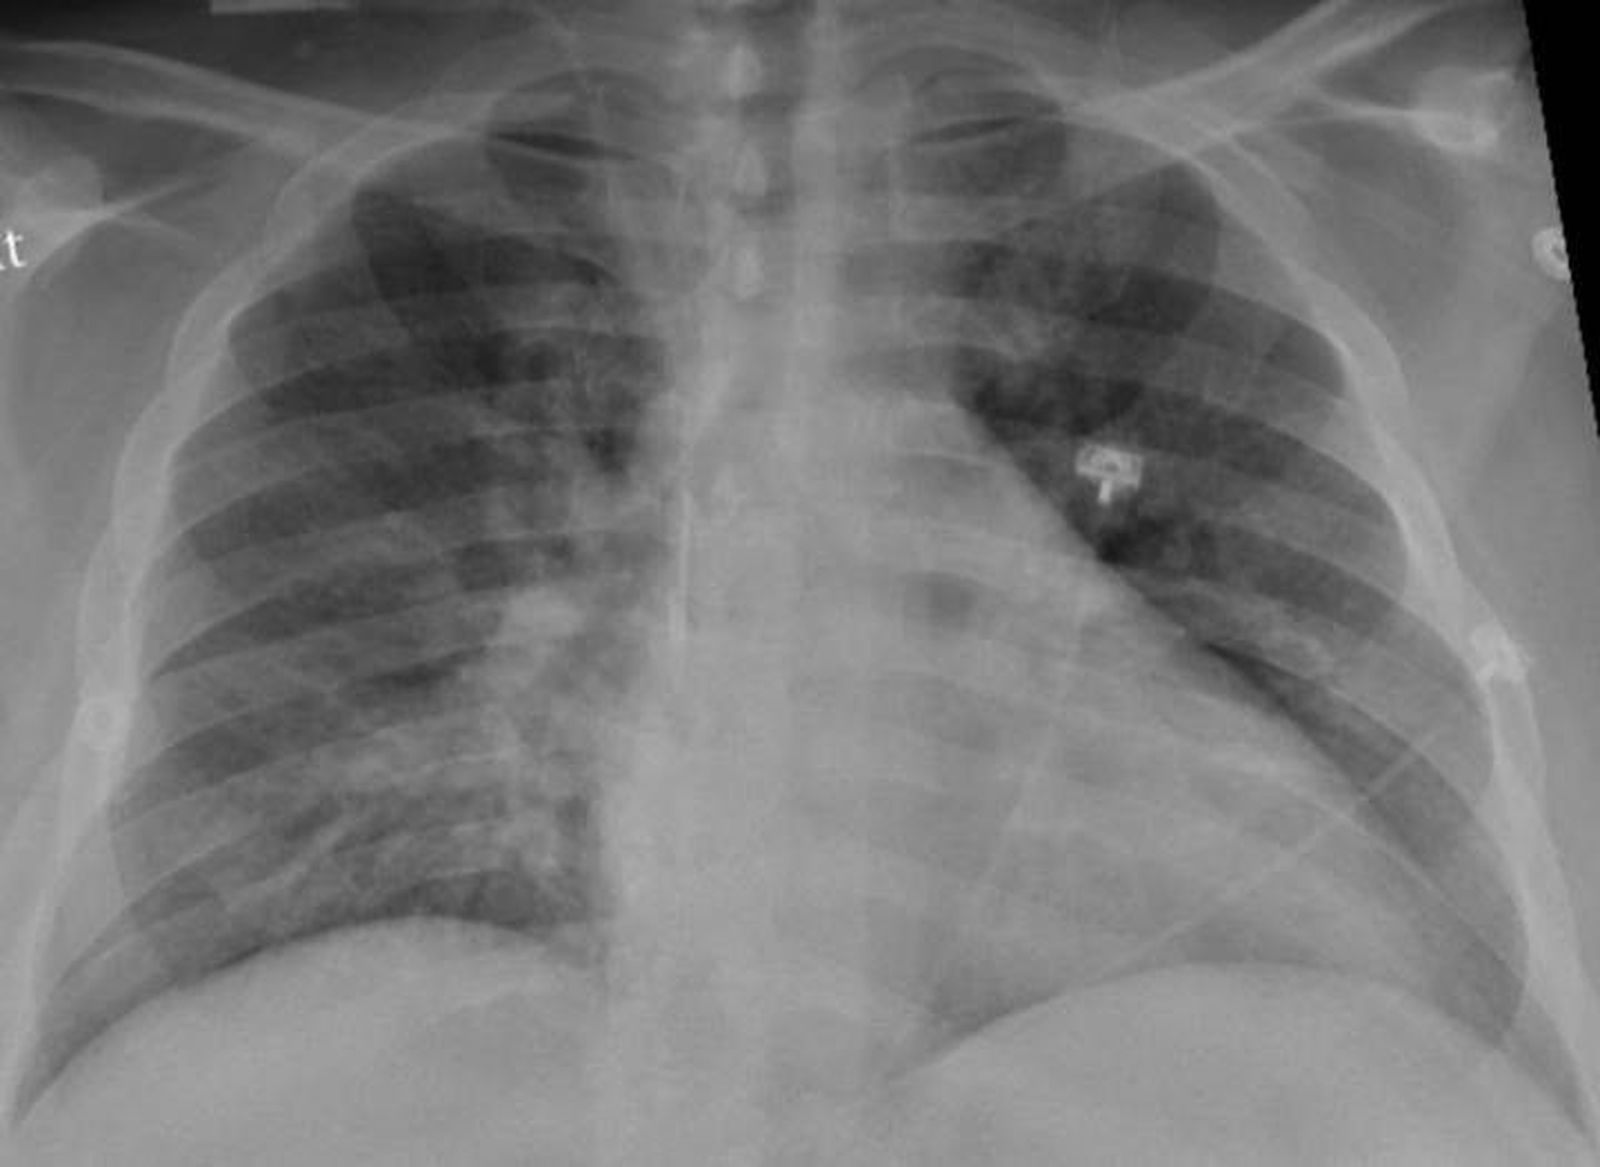

La radiografía de tórax de un paciente positivo de COVID-19 que muestra una neumonía en la parte inferior de los pulmones.